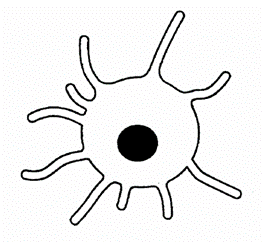

午前-11

免疫に関わる細胞を模式図に示す。この細胞の機能はどれか。1つ選べ。

a. 抗原提示

b. 抗体産生

c. 補体産生

d. 好中球遊走

解答を見る

a